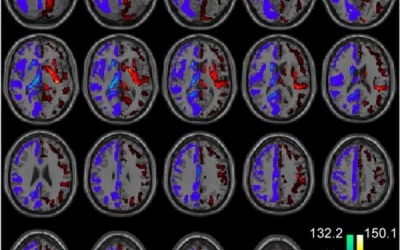

Nhiều người vô tình qua kết quả xét nghiệm máu mới biết bị bệnh bạch cầu (tên khoa học là Leukemia) - một bệnh ung thư ngấm ngầm của tế bào máu và tủy xương. Vì chẩn đoán phát hiện...